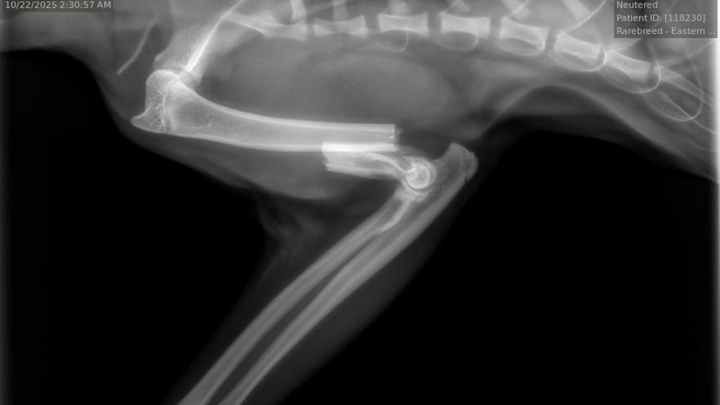

My kitty Benicio broke his arm and needs it to be amputated. He is barely 10 months old and he is the light of my life.

We’ve spent $1700 so far for 1 night at the animal hospital, which does not include the cost of the procedure, and that is $100 less than my monthly fixed income. Please help me keep him with me.